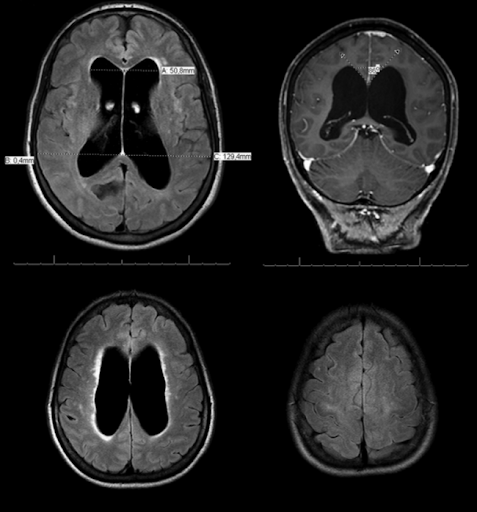

- Η μαγνητική τομογραφία (MRI) μπορεί να καθορίσει εάν οι κοιλίες είναι διευρυμένες, να αξιολογήσει τη ροή του ΕΝΥ και να παρέχει πληροφορίες σχετικά με τον εγκεφαλικό ιστό που περιβάλλει τις κοιλίες.

- Η αξονική τομογραφία (CT) μπορεί να δείξει εάν οι κοιλίες είναι διευρυμένες ή εάν υπάρχει απόφραξη.